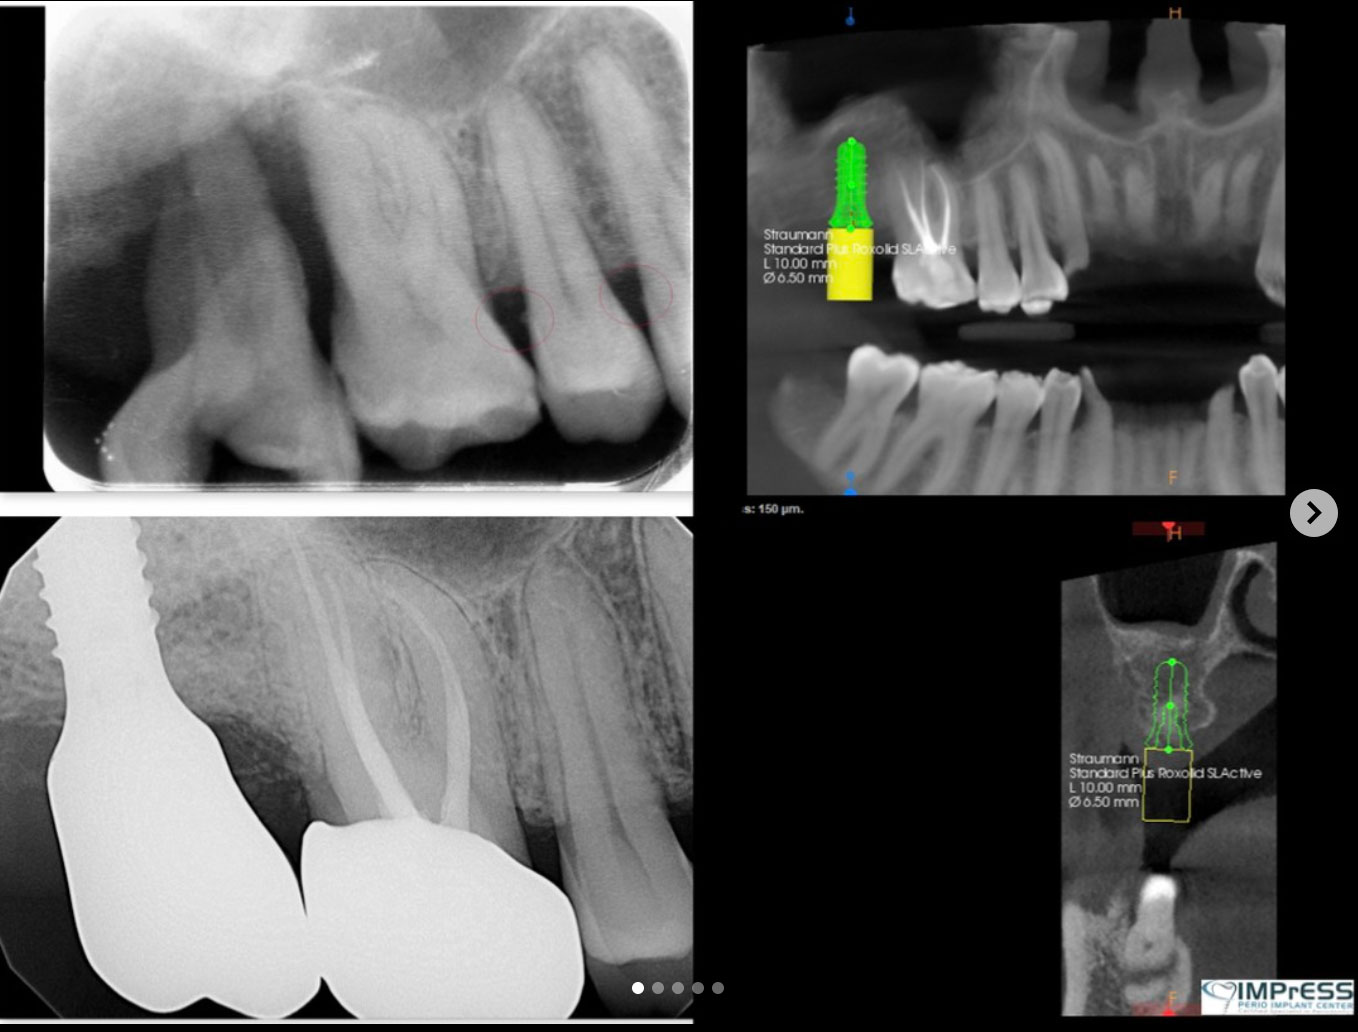

We use digital innovations to digitally plan implant placement to receive the most predictable outcome through:

• Create radiographic and surgical templates from guided surgery software

• Nerve detection, segmentation, and implant placement for prosthetic-driven implant planning with guided surgery software.

• Precision surgical guided placement using restorative-driven three-dimensional imaging and planning allows for more predictable surgical placement.

• High surface digital impression scanning and CAD/ CAM milling allows for precision design and modeling for improved accuracy of both the abutment and restorations. Combining these digital technologies allows us to plan and treat the patient in a more efficient manner with more predictable results.

Straumann offers you important advantages for your missing teeth, with trusted products built on a foundation of quality, scientific research, and leading-edge technology. Why Choose Us?

• Straumann SLActive® is an advanced implant surface designed to bond faster with bone, reduce healing time, and increase the predictability of implant treatment.

• Straumann Roxolid® is the first Titanium Zirconium alloy designed for dental implants and provides improved strength2 over Straumann’s Titanium implants, offering a new option for patients with limited bone or narrow spaces between teeth.